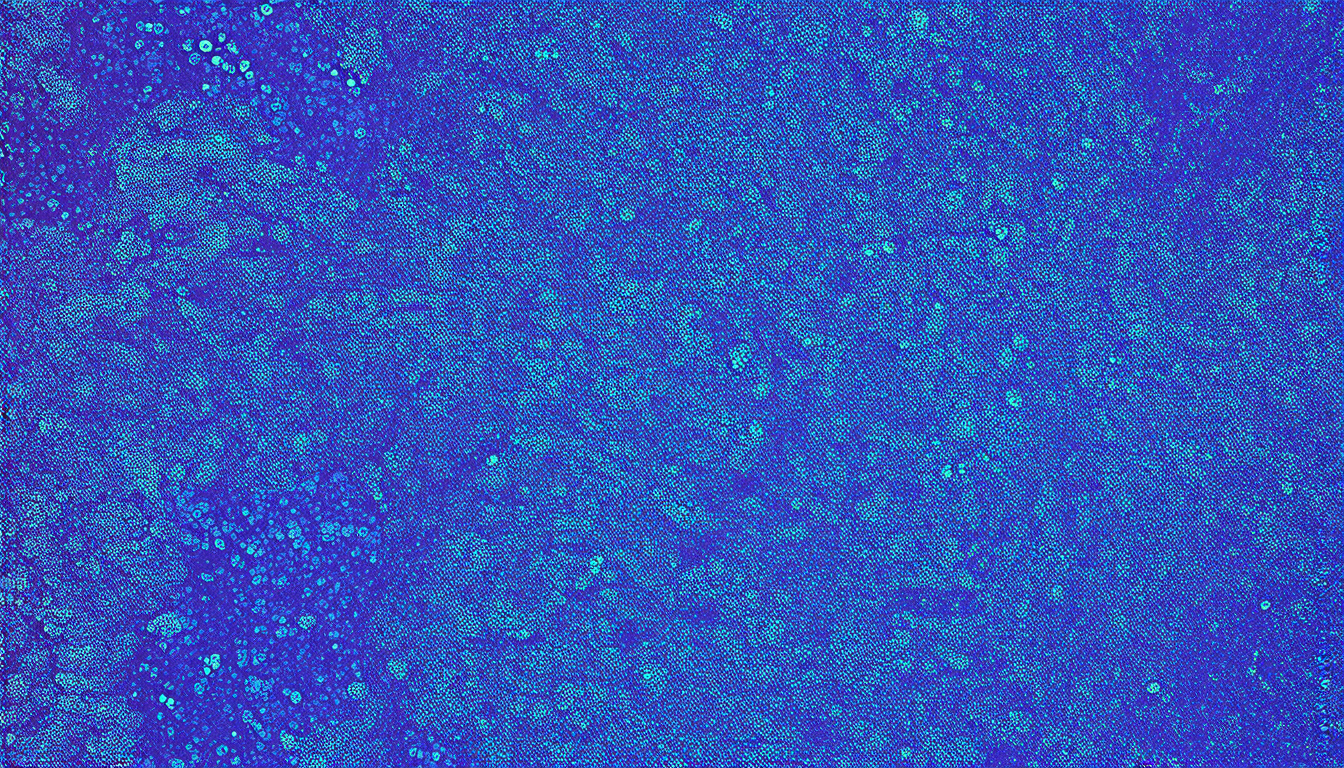

Digital pathology is a rapidly growing field that relies on computers to analyze digital images of tissues and diagnose diseases such as cancer. However, the quality of these images can vary significantly depending on the hospital or scanning protocol used, which can affect the accuracy of diagnoses. This variability is known as domain shift, and it’s a major challenge in developing reliable computer algorithms for medical diagnosis.

The SCDA method was tested on a dataset of skin cancer images from two hospitals in Spain, using a foundation model trained on a large dataset of histological images with paired textual descriptions. The results showed that the SCDA approach significantly improved the accuracy of diagnoses compared to current methods, particularly when only a few reference images were available.